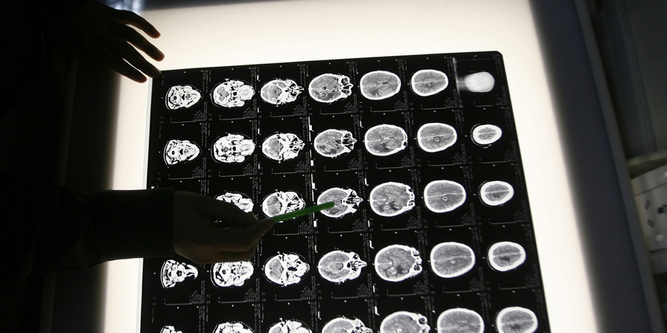

Araştırmacılar, beyindeki demir seviyelerini ölçmek için manyetik rezonans görüntüleme teknikleri kullandılar. Yüksek düzeyde amiloid seviyesi ile birlikte yüksek demir seviyesine sahip kişilerin hızlı bir bilişsel düşüşe maruz kaldıklarını ama amiloid seviyesi yüksek ancak düşük demir düzeyine sahip insanlarda durumun stabil olduğunu tespit ettiler.

Araştırma ekibi, beyin sıvısındaki yüksek düzeyde demirin demans belirtileri ile ilişkili olduğunu bulduktan sonra ölçümlere daha da odaklandı. Yüksek düzeyde amiloid bulunan 117 katılımcının 56’sının PET cihazıyla taramaları yapıldı.

Daha sonra demir seviyelerini ölçmek için MR teknikleri kullanıldı. Araştırmacılar, 6 yıl boyunca bu insanların bilişsel işlevlerini izlediler. Artmış amiloid ile birlikte yüksek demirin, hızlı bilişsel düşüş ile güçlü bir ilgisi olduğunu buldular.